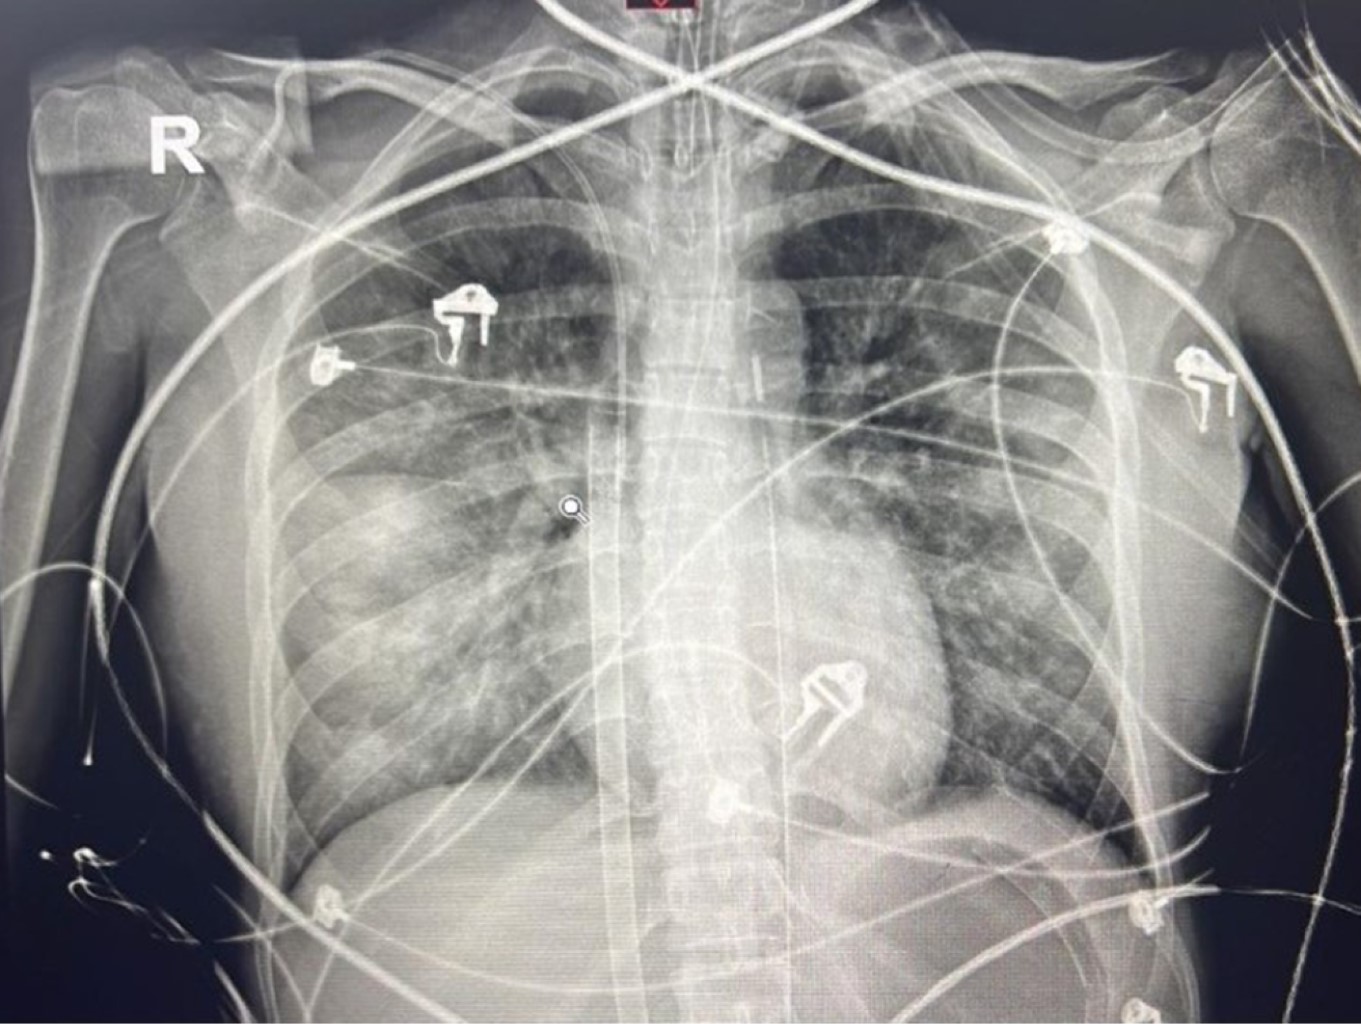

Se realizó cesárea por falta de progresión del trabajo de parto; se obtuvo recién nacido de sexo masculino, peso 3,173 g, talla 49 cm, Apgar 9/9, Silverman 0. Presentó hemorragia postparto de 2,000 mL y choque hipovolémico secundario a atonía uterina, por lo que se le realizó histerectomía subtotal abdominal, embolización selectiva de vasos pélvicos. Requirió de transfusión masiva y empaquetamiento pélvico, se logró contener el sangrado; sin embargo, durante la reanimación mostró datos de vasoplejía a pesar de altas dosis de norepinefrina y vasopresina. Se realizó ecocardiograma transtorácico, el cual mostró ventrículo izquierdo ligeramente dilatado, disfunción sistólica severa, FEVI 18%, contractilidad normal en los tercios basales de la pared lateral, el resto de los segmentos con hipocinesia severa; el ventrículo derecho con función sistólica preservada (TAPSE 19 mm, FAC 48%), aurícula izquierda con dilatación moderada (Figura 1), NT-pro BNP 9,226 pg/mL, troponina de alta sensibilidad 490 pg/mL y proteína C reactiva (PCR) 1.51 mg/L, el electrocardiograma (EKG) con taquicardia sinusal sin datos de lesión isquémica. Se estableció el diagnóstico de Takotsubo (miocardiopatía por estrés).

Se decidió la colocación de soporte con membrana de oxigenación extracorpórea (ECMO), canulación femoral venosa y arterial izquierda, titulando el flujo hasta 2.5 L/min, con poca tolerancia, índice de pulsatilidad inferior a 10 mmHg, se agregó balón de contrapulsación intraaórtica (BIAC) vía femoral derecha (Figura 2). A las 48 horas de su ingreso desarrolló lesión renal aguda y sobrecarga hídrica, por lo que se inició terapia de sustitución renal.

Figura 1

Figura 2